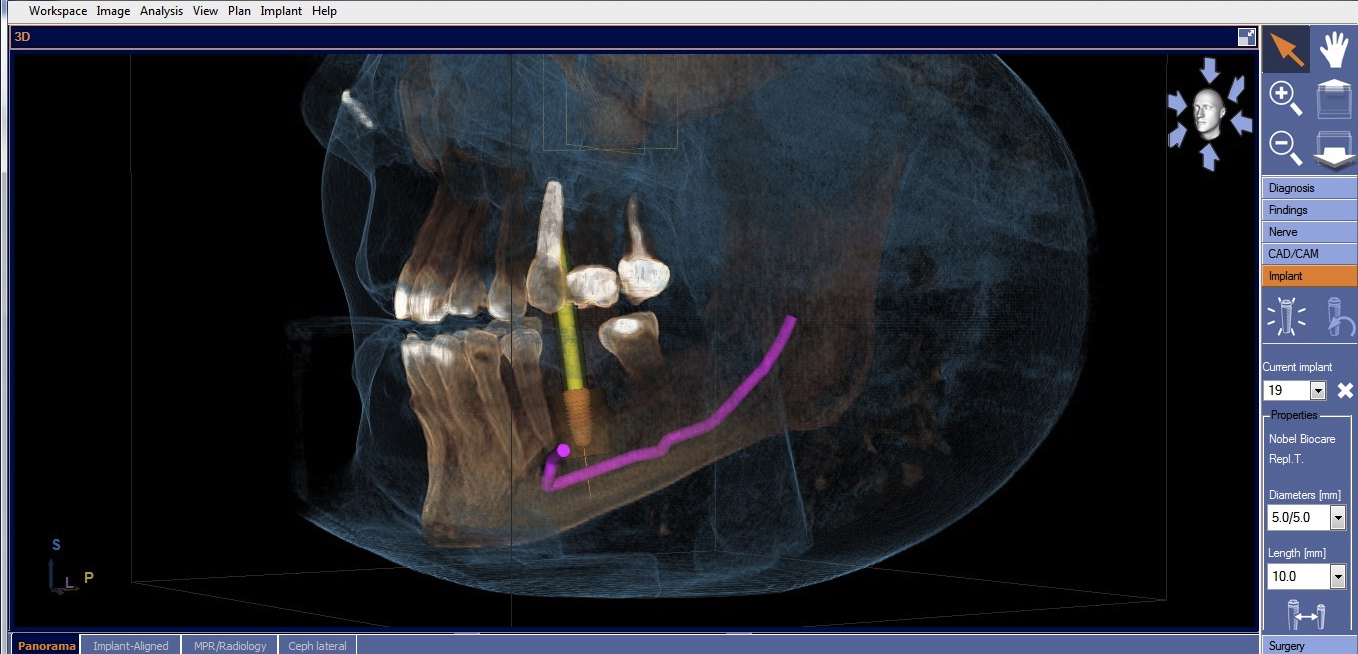

Once the desired restorative outcome is in a digital format, the patient’s CBCT scan is opened in the implant-planning software. If the edentulous space is in the posterior mandible, the inferior alveolar nerve bundle (IANB) is traced so that it is highlighted and avoided by the planned implant (Figure 2). Now, the patient’s digital restoration can be imported. Once imported, most software requires the user to identify corresponding landmarks on the digitized model and on the CBCT to merge the two data sets. It is best to avoid using teeth with crowns or large restorations as landmarks, because they cause distortions in CBCT scans and may result in inaccuracies in data set merges. Once complete, merge accuracy is verified by the user and is either confirmed or reset.

Cone-beam computed tomography (CBCT) with traced and highlighted inferior alveolar nerve bundle (IANB).

Figure 2